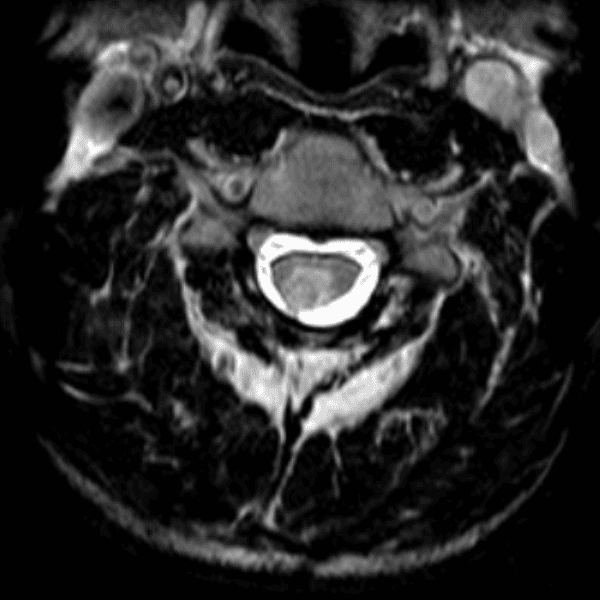

Simulates call by including subtle or difficult cases and some normals.

35 cases